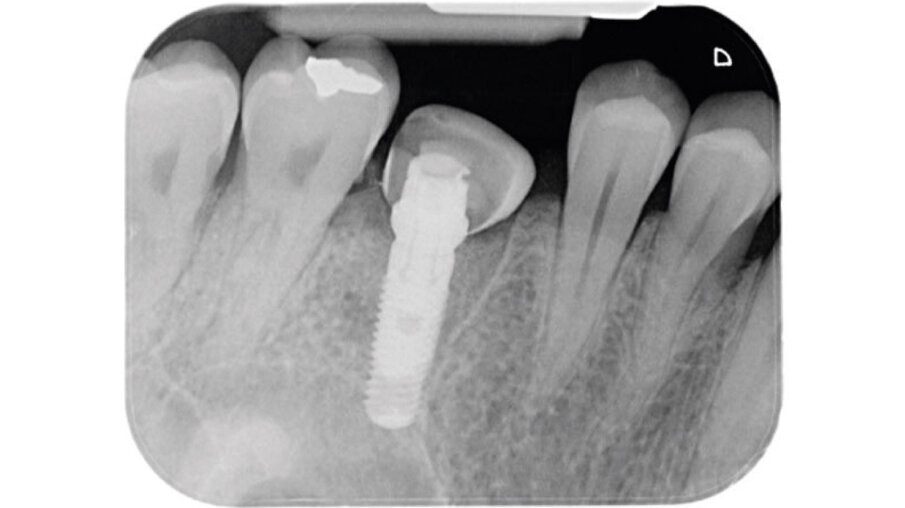

Un paziente maschio (ASA I), senza patologie croniche sistemiche e non fumatore, è stato sottoposto all’estrazione dell’elemento 16 a seguito del fallimento di terapie endodontiche e dell’impossibilità di eseguire un restauro coronale (Figg. 1a, 1b). Nella selezione del paziente sono stati criteri di esclusione: pregressa radioterapia nel distretto testa/collo, assunzione di farmaci che possano indurre ONJ, disordini ematici coagulativi, bruxismo, scarsa igiene orale domiciliare, occlusione instabile, carie non trattate, malattia parodontale non controllata, denti adiacenti a quelli da estrarre con mobilità di grado I o superiore, aspettative di risultato irreali, impossibilità o non propensi a tornare ai controlli di routine e di follow-up. La situazione dei tessuti è stata valutata pre-operatoriamente tramite radiografia periapicala (Fig. 1c) (VistaScan Mini Plus, Dürr Dental). Tramite la CBCT pre-operatoria è stato possibile fare una programmazione implantare. Sulla base dell’anatomia coronale è stata definita la posizione implantare (OnDemand3D, Cybermed), da questa analisi sono stati decisi anche il diametro e la lunghezza dell’impianto.

Fig. 1c - Radiografia con cura canalare non ritrattabile, strumento rotto e probabile frattura verticale con sintomatologia da parte del paziente.